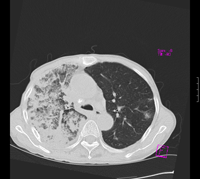

女67岁,咳嗽咯白痰伴纳差一月。右肺呼吸音低可闻及湿罗音。白细胞及淋巴细胞不高,无发烧

1、右上胸廓塌陷,纵隔气管右移

2、病灶靠后方,一般结核多见一点

3、病灶内,纵隔内有少许钙化灶

3楼的肺细支气管肺泡癌也不能完全排除,毕竟患者年纪大,病史短,临床上感染症状不明显,建议短期内复查吧